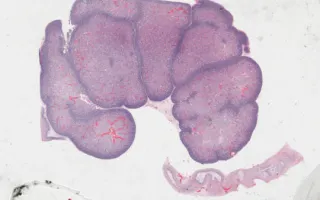

In this syndrome, Wilms’ tumour (nephroblastoma) is common. However, in this case, the finding is nephroblastomatosis, a proliferation of the blastemal component which is considered a precursor to Wilm’s tumour.

The overall findings in this fetus included increased growth parameters, congenital diaphragmatic hernia, nephroblastomatosis, and ovotestes.

This slide shows H&E stain of kidney. See Related Content section for other stains, ovotestis slides, and specimen photograph: